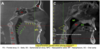

What happened in the images?

perforated lingual cortical plate severe haematoma on the anterior floor of the mouth after implant placement echymosis on the chin after implant placement in the anterior mandible